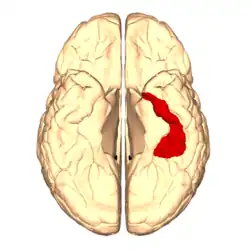

El giro fusiforme presenta un surco central superficial, que determina un sector lateral (externo) y un sector medial (interno), llamados giro fusiforme lateral y giro fusiforme medial. [2] [3] [4] [5]

La porción anterior e interna del giro fusiforme corresponde aproximadamente al área de Brodmann 36 (BA 36). En tanto el surco colateral al área citoarquitectural 35 de Brodmann.